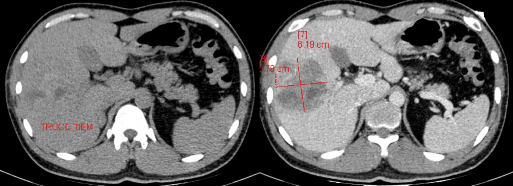

Hình 4.1: CTG độ III, tổn thương dạng đụng dập nhu mô gan HPT VI – VIII trước (T) và sau tiêm thuốc (P).

Nguồn: BN Đặng Mạnh T, 34t Mã HS: 2118010